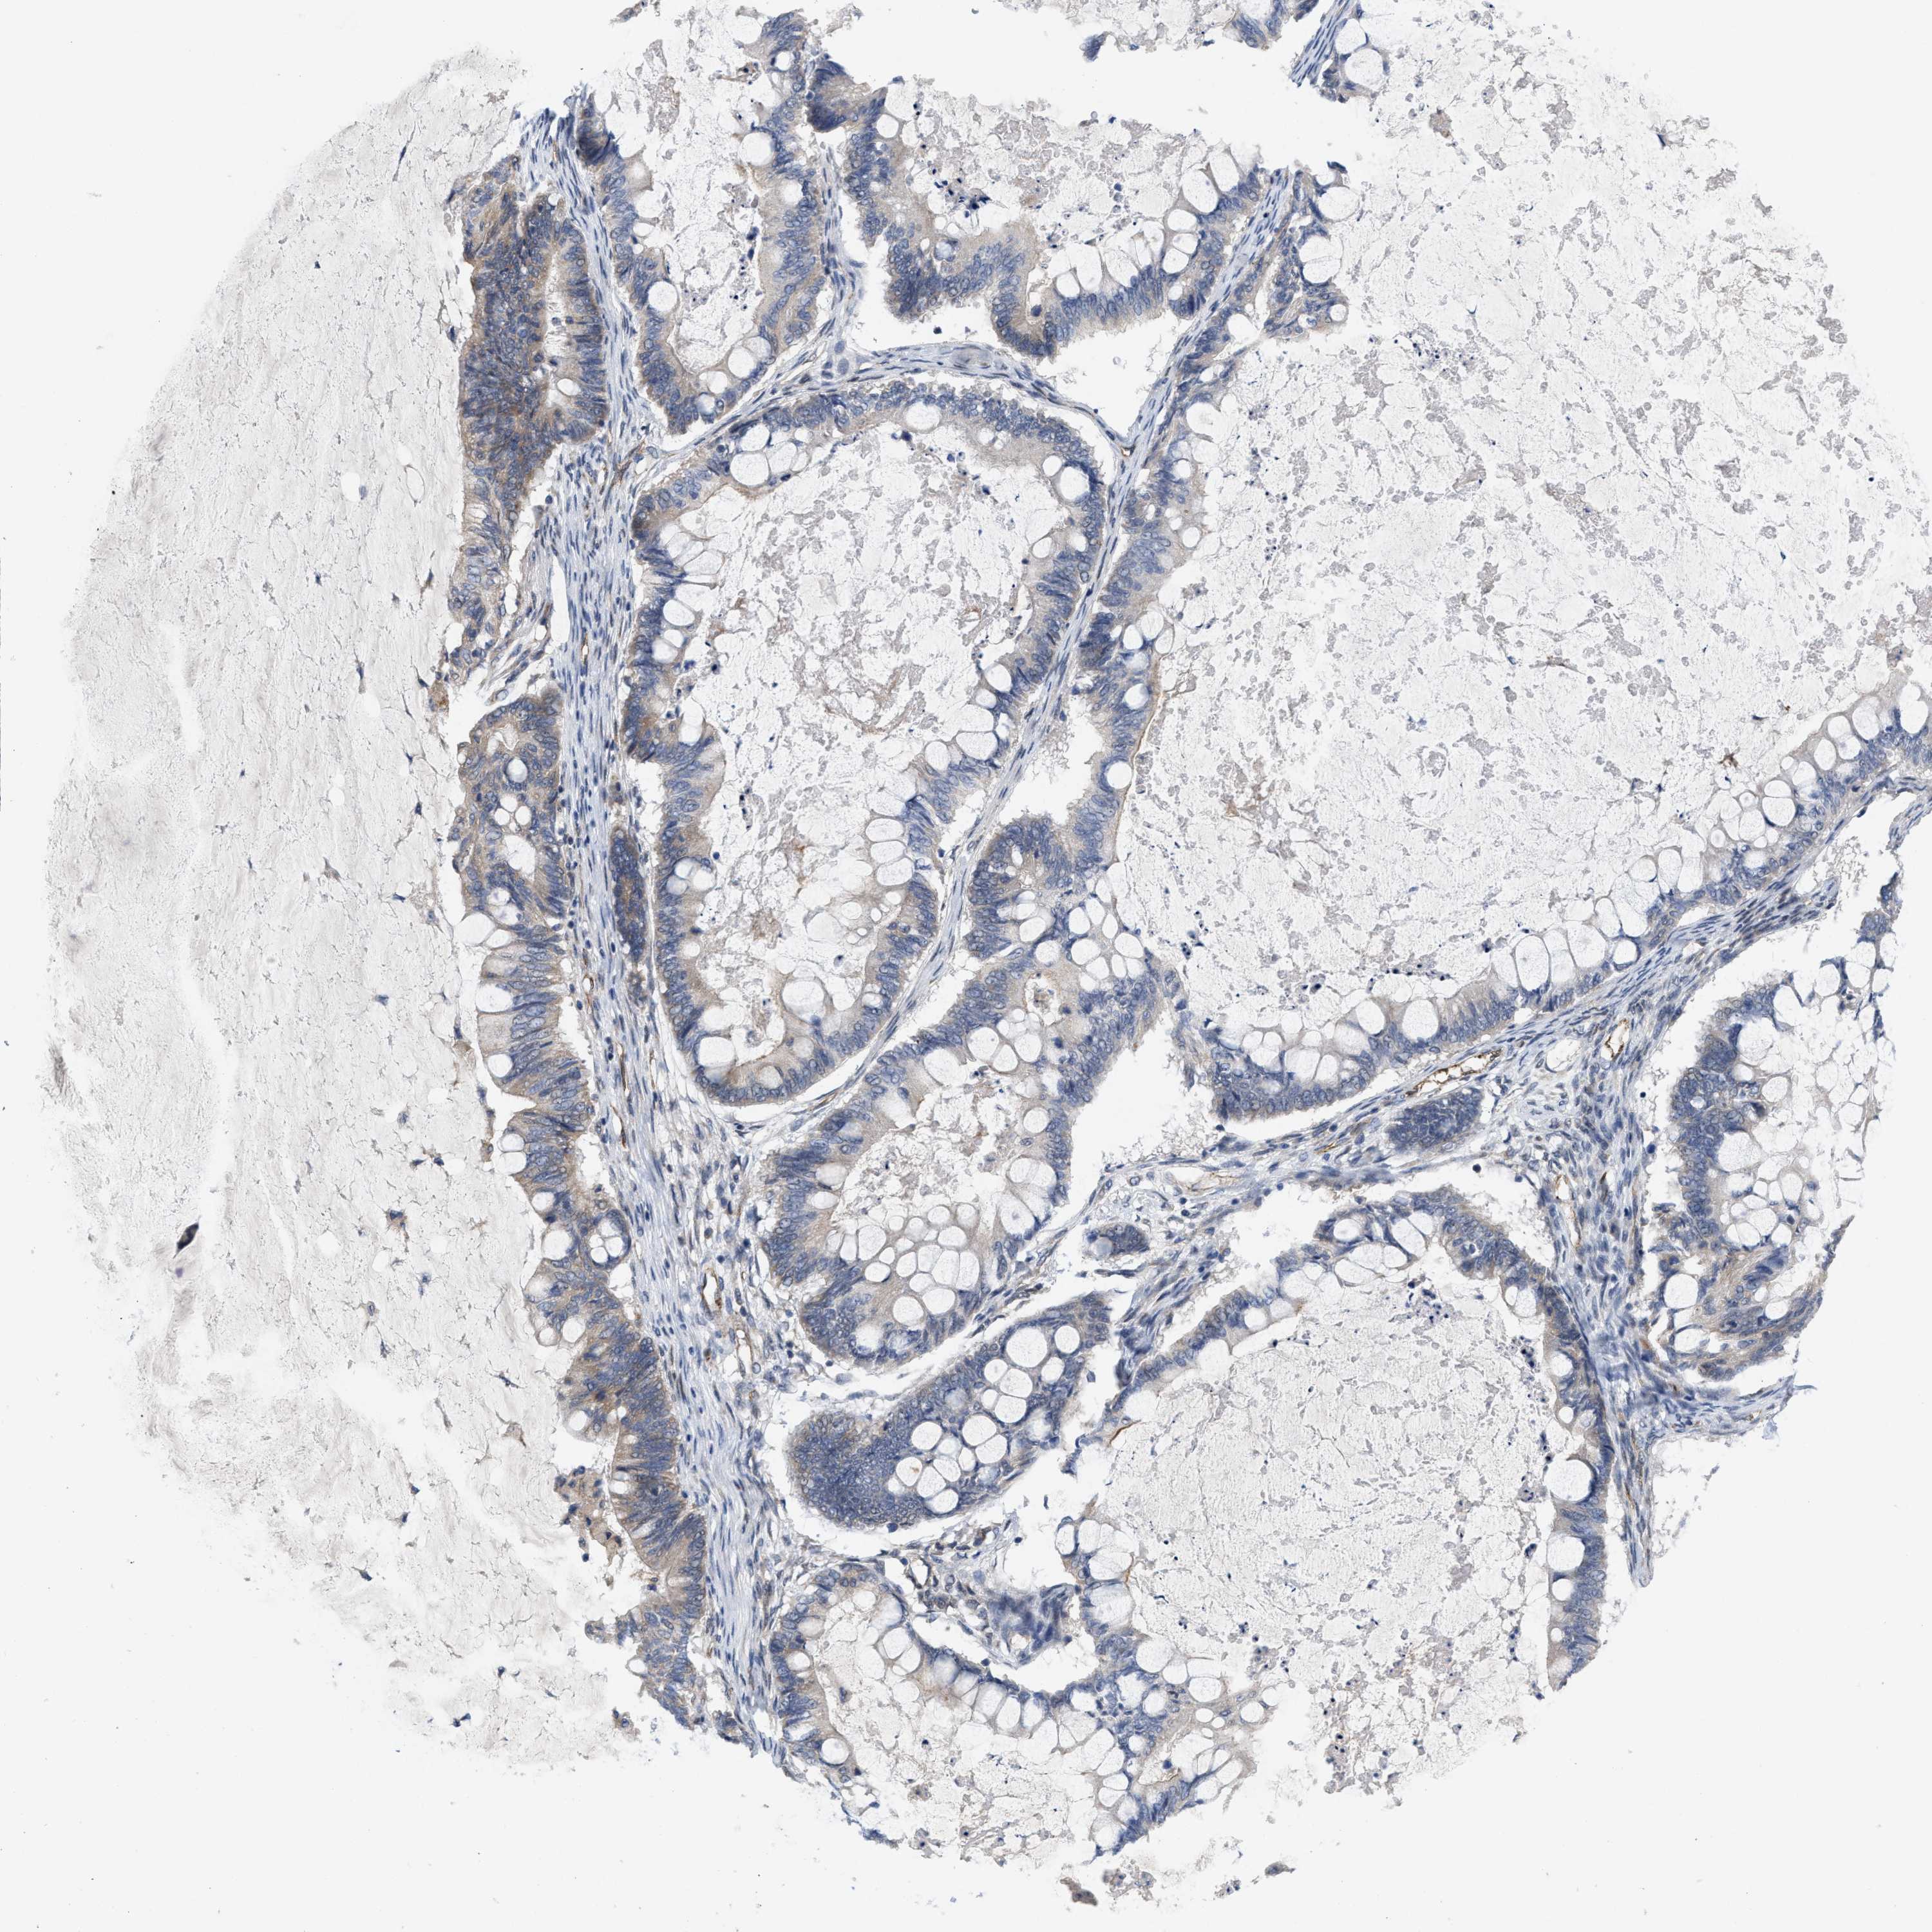

OVARIAN CANCER - Protein expressioni

A mouse-over function shows sample information and annotation data. Click on an image to view it in a full screen mode. Samples can be filtered based on level of antibody staining by selecting one or several of the following categories: high, medium, low and not detected. The assay and annotation is described here.

Note that samples used for immunohistochemistry by the Human Protein Atlas do not correspond to samples in the TCGA dataset.

Antibody stainingi

Antibody staining in the annotated cell types in the current human tissue is reported as not detected, low, medium, or high, based on conventional immunohistochemistry profiling in selected tissues. This score is based on the combination of the staining intensity and fraction of stained cells.

Each image is clickable and will lead to virtual microscopy that enables deeper exploration of all samples and also displays staining intensity scores, fraction scores and subcellular localization as well as patient and tissue information for each sample.

Antibody HPA019460

Staining

High

Medium

Low

Not detected

Intensity

Strong

Moderate

Weak

Negative

Quantity

>75%

75%-25%

<25%

None

Location

Nuclear

Cytoplasmic/membranous

Cytoplasmic/membranous,nuclear

Cystadenocarcinoma, serous, NOS

Carcinoma, endometroid

Cystadenocarcinoma, mucinous, NOS

Carcinoma, NOS